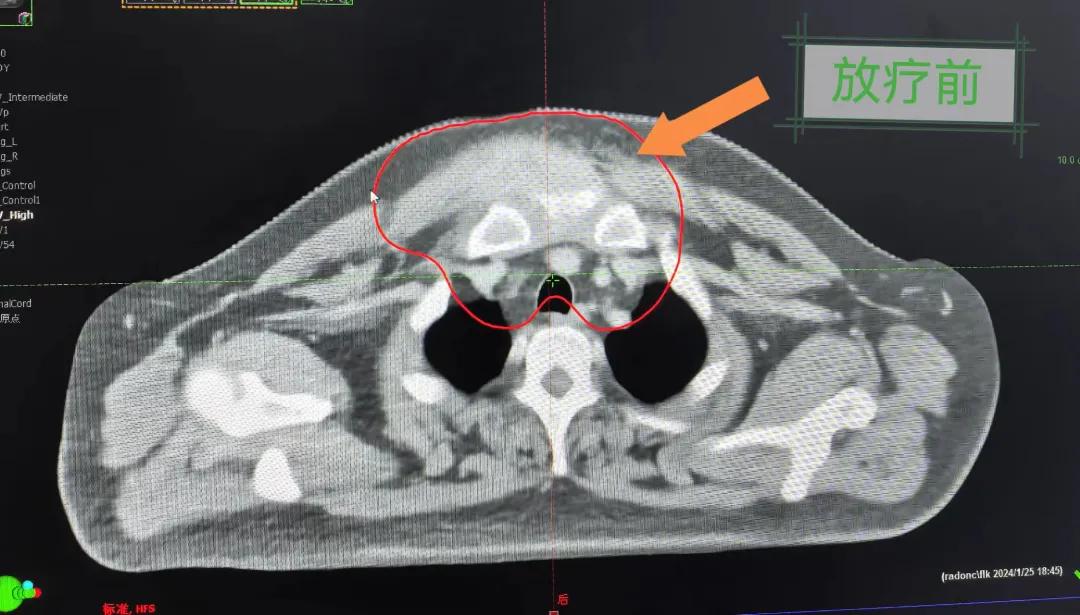

患者經(jīng)多方咨詢與打聽,在家屬的陪同下來到市二院放療科找到趙亮主任尋求幫助。入院后迅速完善了相關檢查,診斷為罕見的“胸壁腫瘤”。因腫瘤體積大,侵犯周圍組織,手術治療難度較大,經(jīng)院內(nèi)多學科會診后,決定采用無創(chuàng)的局部放射治療。在初步告知患者及家屬治療方案時,病人及家屬都擔心預后及放療可能引起的不適,趙亮主任詳細且耐心的向家屬和病人講述放療過程中可能出現(xiàn)的不良反應,確保讓他們安心治療。

隨后,趙亮主任帶領放療團隊以最快的速度完成了患者的放射治療計劃,在保證放療精準打擊腫瘤的同時,利用先進的三維立體精確放療技術,最大限度的避免心臟、肺部的損傷發(fā)生,整體治療精準度達到1mm以內(nèi)。經(jīng)過10次的放射治療后,患者疼痛已明顯減輕,胸部腫物肉眼可見的縮小,患者及家屬臉上終于露出久違的笑臉。

治療期間,患者沒有出現(xiàn)明顯不適,治療結束后,患者胸壁腫物由最初8cm縮小至約1cm,后患者至外科行手術治療。